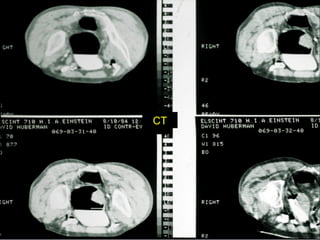

Câncer de Bexiga Estudos de imagens Diagnóstico Ultrassonografia Urografia excretora Estadiamento CT RNM Rx tórax  Cistoscopia + biópsia + biópsias randomizadas

CT